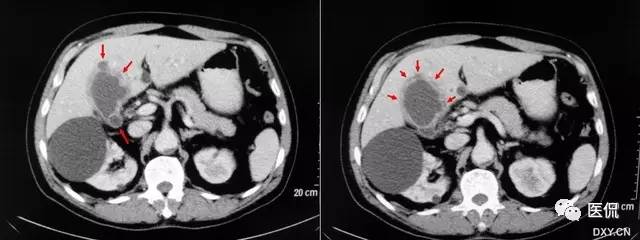

【影像表现】在CT或MRCP及T2W I上增厚的胆囊壁中多发、微小圆点状的高信号囊腔,大小2~7mm,一般为4mm,形似珍珠项圈。

【征象解释】胆囊肌层及上皮增生、肥大,粘膜外翻进入肌层形成罗-阿氏窦。因为罗-阿氏窦内充满胆汁,在MRCP或T2WI增厚的胆囊壁内可呈显著高信号点。

【讨论】胆囊腺肌瘤病是胆囊上皮及肌层增生,粘膜向增厚的肌层内突出或穿过肌层形成罗-阿氏窦,是胆囊的一种常见疾病。发病率为2.8%~5%或更高,常表现为胆囊壁的局限性或弥漫性增厚,因此必须与胆囊癌鉴别。

胆囊腺肌瘤病有3种分型:弥漫型、节段型、局限型。因为有这种形态变异,它可表现为弥漫性胆囊壁增厚或局限性、局灶性损害,可能被误以为胆囊癌口因此,胆囊腺肌瘤病与胆囊癌的影像学区别是非常重要的口病理学上,胆囊腺肌瘤病的特征表现是增厚的胆囊肌层中看到罗-阿氏窦,罗-阿氏窦的发现是诊断胆囊腺肌瘤病的关键点。

在静脉胆道造影中充满造影剂的罗-阿氏窦被认为是胆囊腺肌瘤病的特异性病征,也称为珍珠项链征。然而,罗-阿氏窦的显示率相对较低(大约5%),因为胆囊不可能一直充满造影剂。虽然,静脉胆道造影检查前服脂肪餐可能改善罗-阿氏窦的显示,但还是不够;而且,静脉胆道造影用的造影剂频繁发生变态反应,有时可能导致过敏性休克口目前,对于胆囊疾病的非创性且方便的检查方法首选US。虽然US对胆囊腺肌瘤病的诊断有一定的敏感性,但因为它依赖操作者的经验,所以有一定的不确定性,其观察视野小、肠道气体、肥胖及与结石共存使US在胆囊壁的评估仁有一定困难。因此,Us在胆囊腺肌瘤病的诊断准确率只有60%。

CT及MRI可发现胆囊壁的局限性或弥漫性增厚,以及病变处勒膜层的早期强化和浆膜层的延迟强化,但很难与胆囊炎和胆囊癌相鉴别。罗-阿氏窦内含胆汁,在T2WI上表现为胆囊壁肿块内或增厚的胆囊壁内直径为4~7mm的类圆形高信号灶;在动态增强扫描图像上,表现为增强的肿块内或增厚的胆囊壁内不强化的低或无信号灶。由于动脉期CT或MRI增强比较低的对比度与空间分辨率,较多小的罗-阿氏窦无法显示,动脉期CT或MRI能鉴别最小直径5mm的罗-阿氏窦,而MRCP能鉴别的最小直径是3mm,MRI重T2加权快速自旋回波序列在胆囊腺肌瘤病中的诊断价值已经被研究,因为罗-阿氏窦充满胆汁,在增厚的胆囊壁中可呈显著高信号点。单次激发快速SE序列MRCP很少出现运动伪影和磁敏感性伪影,对于显示罗-阿氏窦,单次激发快速自旋回波序列MRI比动脉期CT或MRI增强扫描及重T2加权快速自旋回波序列更可靠。

珍珠项链征在诊断胆囊腺肌瘤病方面特异性较高,达92%。因此,在诊断胆囊腺肌瘤病和鉴别胆囊腺肌瘤病与胆囊癌中是较为特异性的。MRCP对于显示<3mm的罗-阿氏窦有一定困难。胆囊囊壁内钙化在CT上能帮助诊断胆囊腺肌瘤病,而在MRCP上可能成为一个陷阱。浓胆汁比正常胆汁有更短的T1时间,浓胆汁患者罗-阿氏窦可能无法鉴别。因此珍珠项链征在这些患者中不能被鉴别,特别是用长回波时间的MRCP技术。浓胆汁T1时间短,在T1W I中显示为高信号强度。因此T2W I可能对证明罗-阿氏窦有帮助。因为胆囊壁内脓肿或黄色肉芽肿的存在。黄色肉芽肿性胆囊炎可能显示类似的珍珠项链征。胆囊腺肌瘤病与胆囊癌有时可以共存,员然很少见,但有这样的病例限制了珍珠项链征鉴别胆囊腺肌瘤病与胆囊癌。因此,那些局部胆囊腺肌瘤病的患者特别要密切随访检查,即使在MRCP图像上已明确异示珍珠项链征。